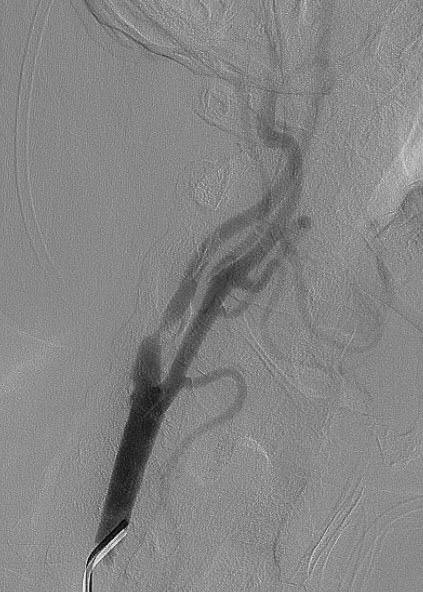

62-летний пациент жаловался на частые головные боли, головокружение и появление «мушек» перед глазами. Врачи провели ряд обследований и выявили критическое сужение (на 90%) правой внутренней сонной артерии. Было принято решение в кратчайшие сроки провести операции по установке стента для восстановления нормального кровотока.

После успешного лечения и контрольного обследования не было выявлено никаких нарушений кровообращения. Пациента выписали в удовлетворительном состоянии.

Перед стентированием проводят ангиографию — рентгенологический метод исследования, позволяющий определить характер, местоположение и степень стеноза.

- Проводится ангиографический контроль в том числе интракраниальных отделов сонной артерии